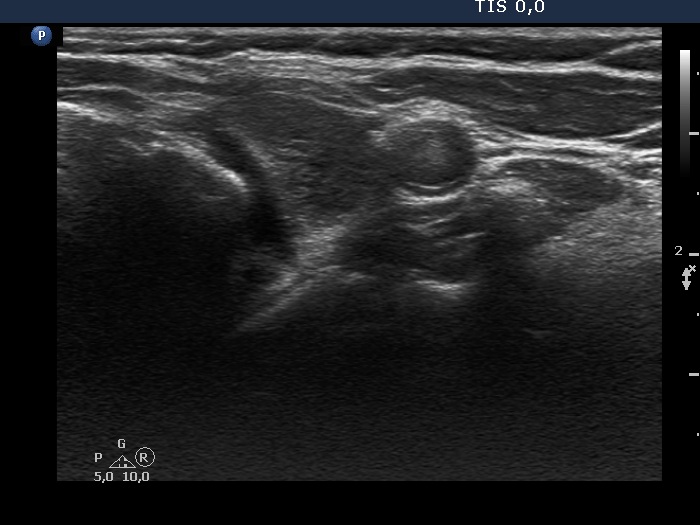

Second examination 3 years later (second, fourth and sixth rows of images):

Ultrasonography. Compared with the previous examination, both the number and the size of discrete lesions in the thyroid have increased.